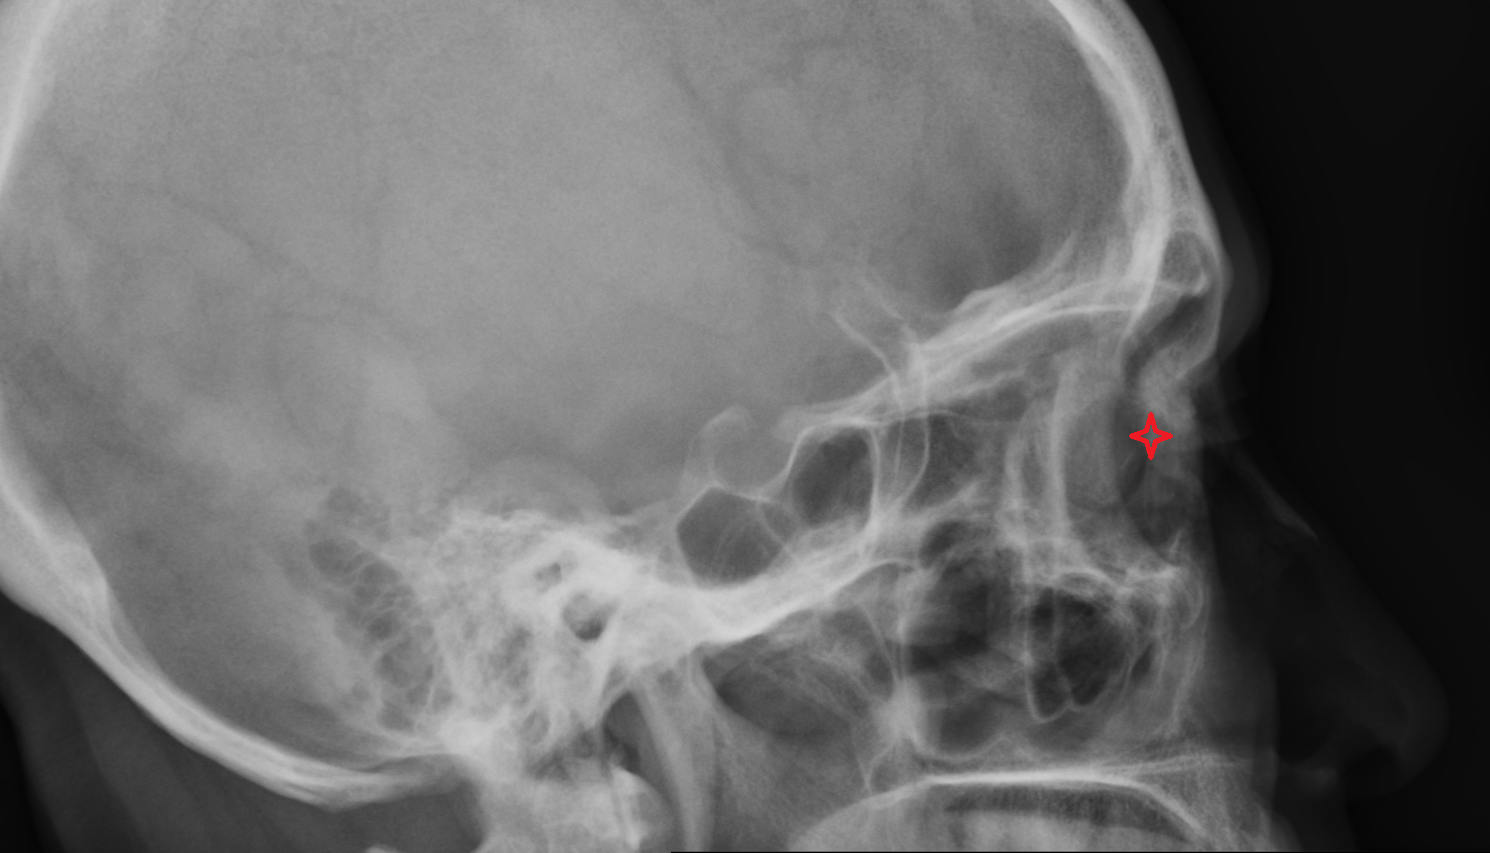

- Temporomandibular joint

- Mandibular condyle

- Mandibular fossa

- Mastoid process

- Petrous part of temporal bone

- Squamous part of temporal bone

- Zygomatic process of temporal bone

- Zygomatic arch